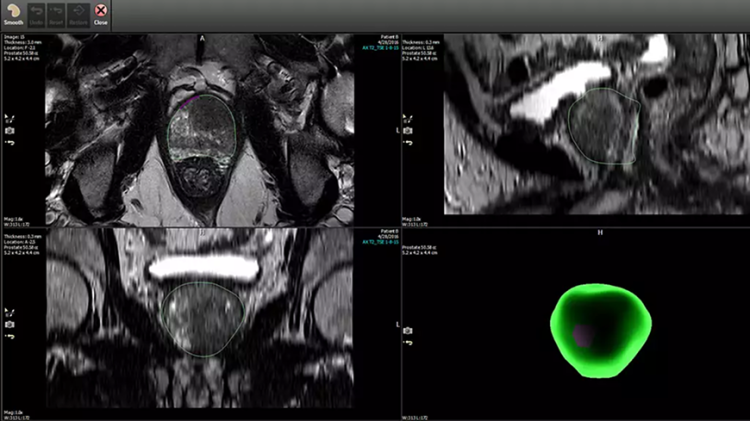

DynaCAD 泌尿外科与放射学中使用的 DynaCAD Prostate 配合使用,为泌尿科医生提供一种存储、审查和管理综合诊断和治疗数据的简单方法。它提供了专门用于泌尿科检查的查看布局和工具。

放射科使用 DynaCAD Prostate 定义前列腺边界和目标后,DynaCAD 泌尿科会显示结果信息以供泌尿科检查。专用工具允许您根据需要编辑前列腺分割,并根据先前的活检程序核心位置添加目标。这为使用飞利浦 UroNav 的融合引导活检创建了一个即用型计划。